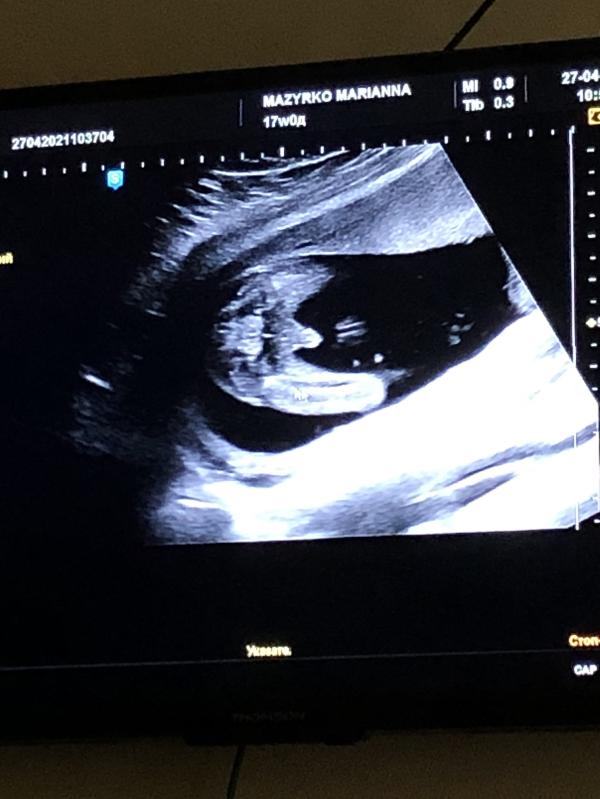

27.04.21. Срок 17 недель

С первой секунды,Марианна Александровна увидела нашего мальчика. Показала нам, «то самое» пикантное место)))У мужа не осталось сомнений)) 100% boy💙

Дочка была с нами. Половину не поняла,но сидела, внимательно наблюдала))В очередной раз остались довольны, посмотрели каждую косточку))

С нашим сыночком все хорошо, развивается по сроку. Можно больше не переживать. И НИПТ тоже тому подтверждение.

Шейка хорошая -38мм, зев закрыт.

ПДР совпадает- 5 октября

Записали диск с комментариями. Фото распечатали. На телефон тоже много сняла. Фото прикреплю